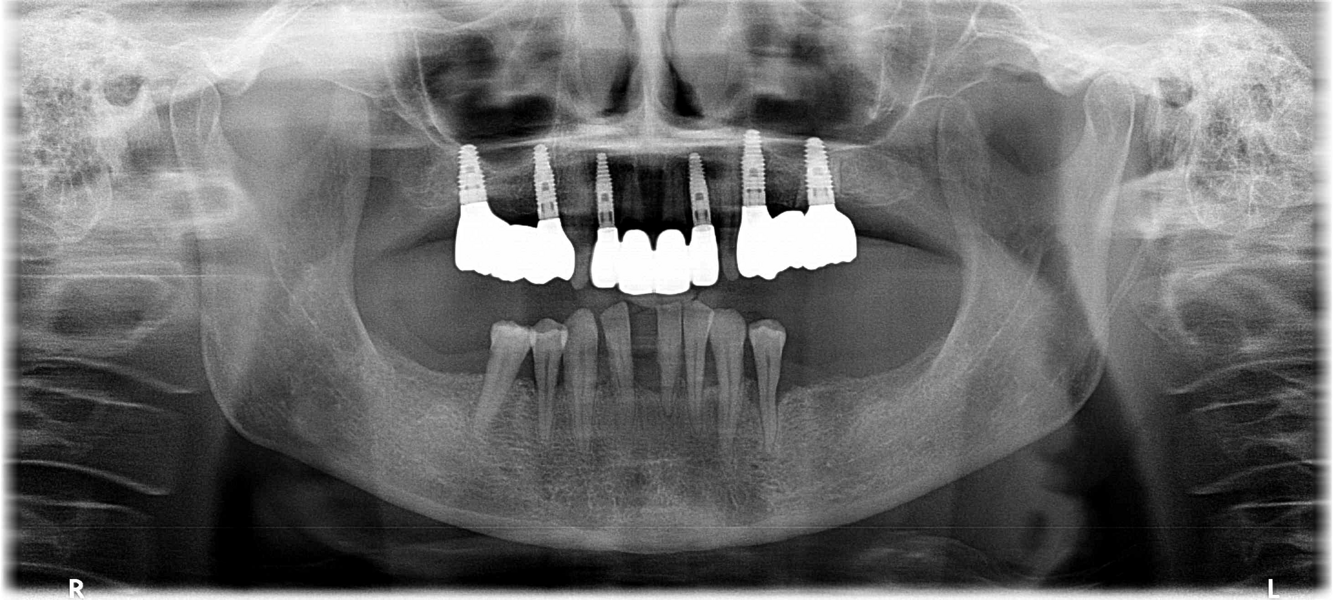

Definitive prosthetic treatment was performed after completion of implant healing with three CAD/CAM-fabricated monolithic zirconia bridges (DD cubeX2, Dental Direkt). The bridges were screwed on to BEGO titanium base abutments (Figs. 14–16). Good fit of the prosthetic superstructures was displayed in the radiograph after placement (Fig. 17). The two-year follow-up examination in July 2019 revealed excellent aesthetic and clinical soft-tissue conditions (Figs. 18–20). No radiographic bone loss had occurred at the implant sites (Fig. 21). Neither the submerged central incisors nor the distobuccal molar root displayed any signs of periapical inflammation, and the patient reported no complications. The patient’s oral hygiene had improved significantly during the follow-up period.

Fig. 17: Final radiograph with definitive prosthetic superstructures in place.

Fig. 21: Radiographic control after the two-year follow-up period, showing no visible bone loss at the implant sites and no signs of periapical inflammation at submerged roots.